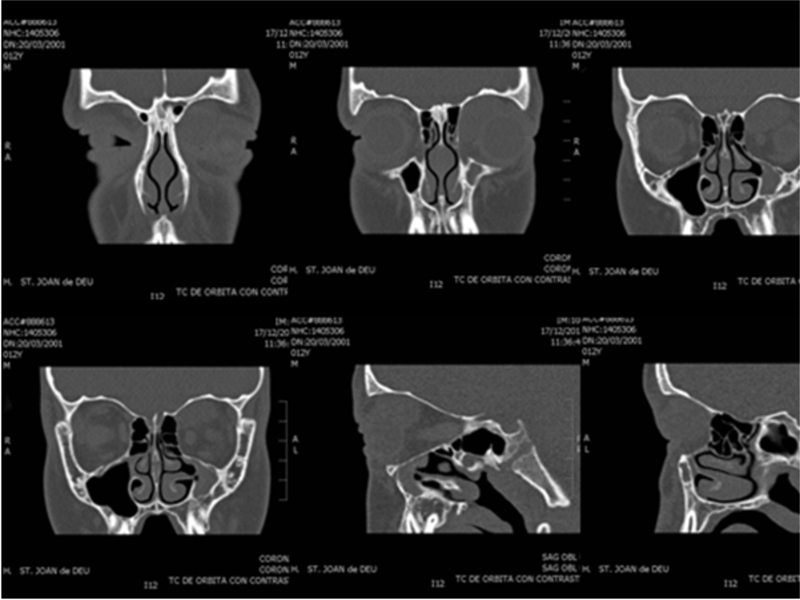

Embrionario (80%). El más frecuente y de mejor pronóstico (94% supervivencia a los 5 años). Localización: cabeza, cuello y órbita. La histología muestra células fusiformes a redondas que muestran características de músculo estriado en varios estadios de desarrollo embrionario, de citoplasma eosinófilo, y presencia de estriaciones cruzadas (Figura 3).

Figura 3. Histología de rabdomiosarcoma embrionario (tinción H/E): Tumoración constituida por una proliferación de células fusiformes, densamente celulares, agrupadas alrededor de estructuras vasculares y con zonas de fondo claramente mixoide. Las células tumorales muestran núcleos elongados de cromatina fina, pequeño nucléolo y citoplasmas mal delimitados, con abundantes figuras de mitosis.